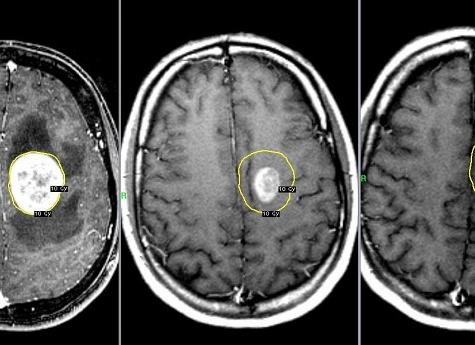

Наиболее современный метод диагностического обследования, который, в свою очередь, позволяет получить наиболее достоверную информацию не только о строении, но и о полной работе органа – МРТ. При помощи этого метода диагностического обследования, можно выявить нарушения не только в печени, но и в иных органах, например: мочевом пузыре, жёлчном пузыре, 12-перстной кишке и т.д.